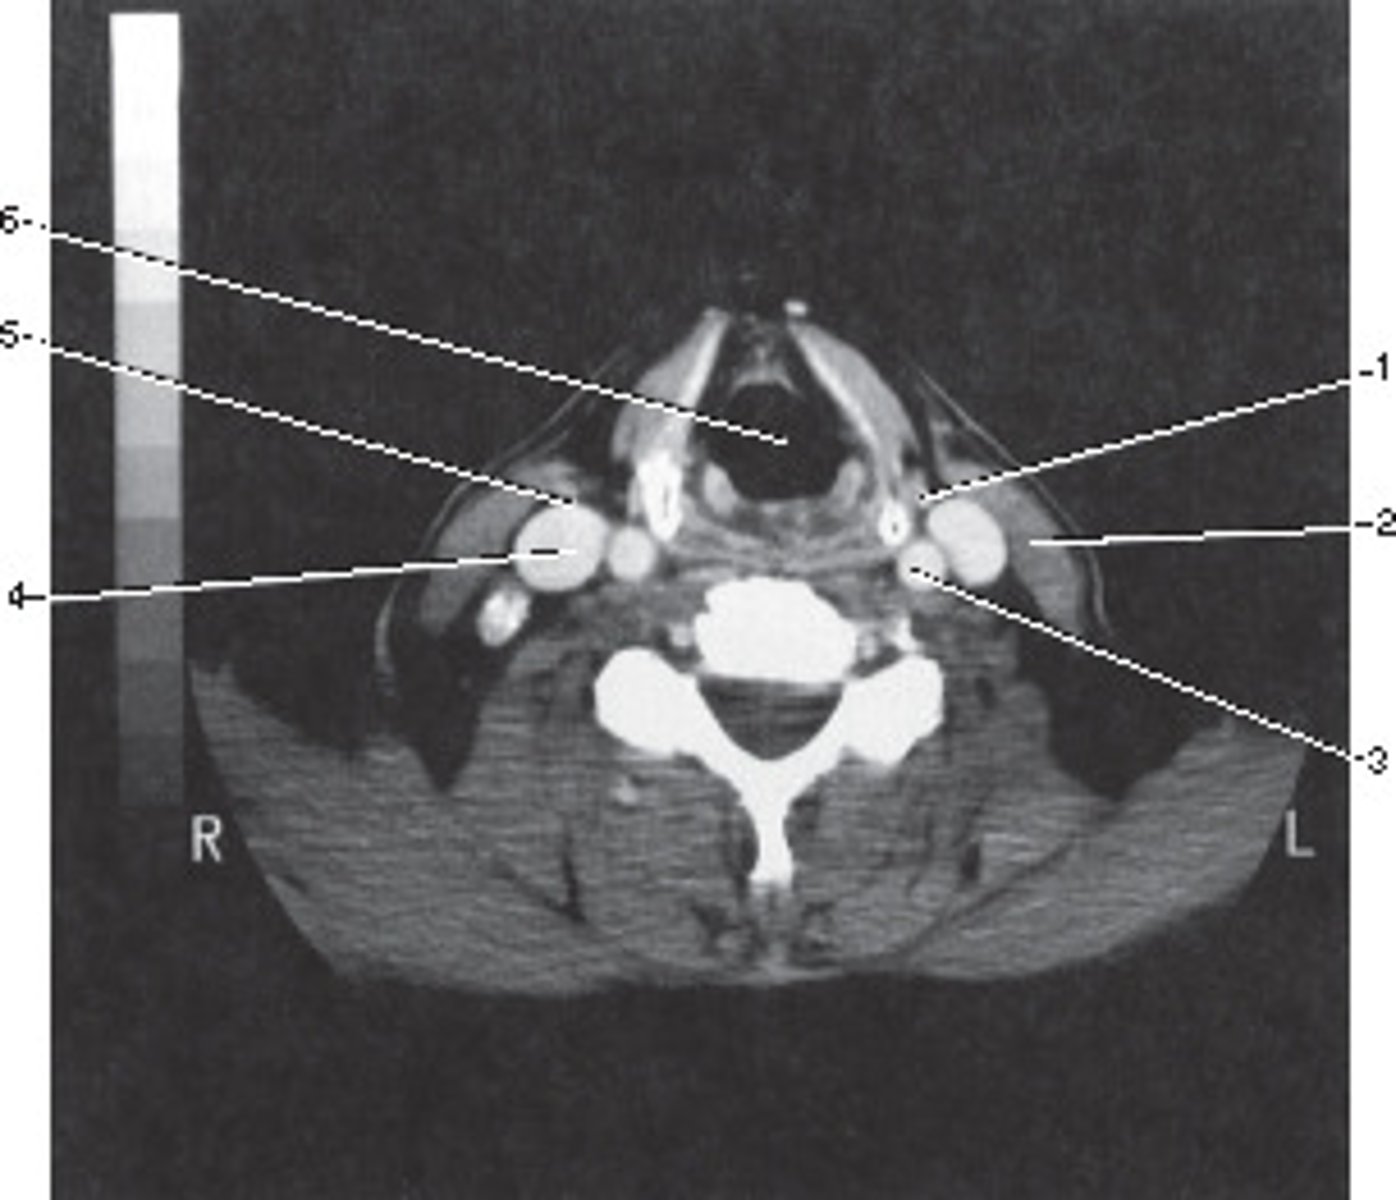

Enlarged Thyroid

<p>What pathological process best describes the abnormal finding in this image?</p>

Thyroid Gland

<p>Number 1 corresponds to which of the following?</p>

Vertebral Artery

<p>Number 3 corresponds to which of the following?</p>